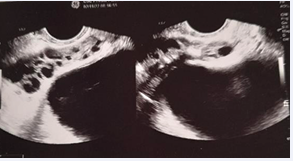

Figure 11 : Transrectal Prostatic Pchography: Seminal Vescicle Important Dilatation